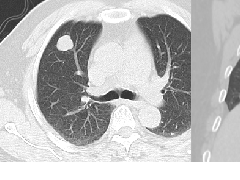

MRI 表现:鼻咽后壁及两侧壁不规则软组织肿块,信号多较均匀,T1WI 像呈等信号,T2WI 像呈稍高信号,DWI 像为明显高信号。增强扫描肿块常轻-中度均匀强化,液化坏死少见。颈部淋巴结肿大常见。肿大淋巴结多边缘规则,内部密度或信号均匀,增强扫描轻度强化。对邻近组织侵犯少,肿块与咽后壁头长肌等分界清楚,多无颅底及相邻骨质破坏。鼻咽部肿块虽较明显,但咽旁间隙较清晰,或只有受压改变。

MRI 表现:早期表现为鼻咽顶后壁轻度软组织增厚、突起,表面不规则、边界不清;咽隐窝变浅甚至消失,鼻咽轮廓改变,双侧结构不对称;进展期肿瘤增大向周围组织、结构浸润生长,并可破坏颅底骨质结构,以中线部蝶骨体和枕骨斜坡最常见。肿瘤在 T1WI 像上呈中等或中低信号,T2WI 像上呈中等或中高信号,边缘模糊呈浸润状;增强扫描多呈明显强化,肿块内坏死区无强化。颈部较小的转移淋巴结边缘多较清楚、信号均匀;较大的淋巴结中央常见液化坏死,多发增大的淋巴结可融合呈巨大的肿块,信号不均匀。